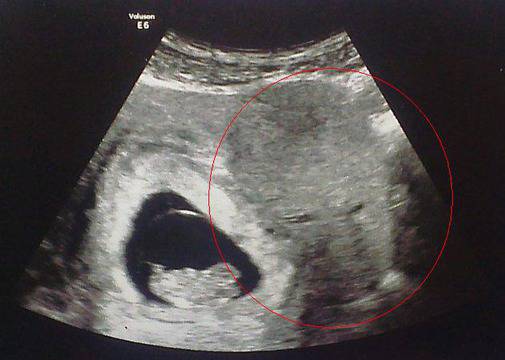

На снимката съвсем ясно се вижда човешко лице

Когато бременната в деветата седмица Ан Клюлоу от Сток-он-тренд (графство Стафордшир, Великобритания) отива на консултация, лекарят преглежда бременната на ехограф и констатира, че бременността се развива съвсем нормално. По време на прегледа докторът прави сника на плодът и я дава на бременната Ан. Когато тя се прибира вкъщи и вижда снимката, я побиват тръпки. На фотото ясно се вижда човешко лице – с очи, нос и уста. Образът не се е виждал на монитора, но на принтираната снимка, той се различава много добре.

Виждате ли образа?!

На много хора им е трудно да различат бебе в по-ранния етап от бременността на ехографска снимка. Особено трудно мъжете успяват да различат кое точно от тъмните петна е плодът. Но на тази снимки всички точно и ясно различават човешка глава с лице.

Ан Клюло, която не е особено религиозна има обяснение за образа появил се на кадъра: „Аз мисля, че това е ангелът пазител на нероденото ми дете. Той бди над бебето ми.“ споделя майката, цитирана от yahoo.de.